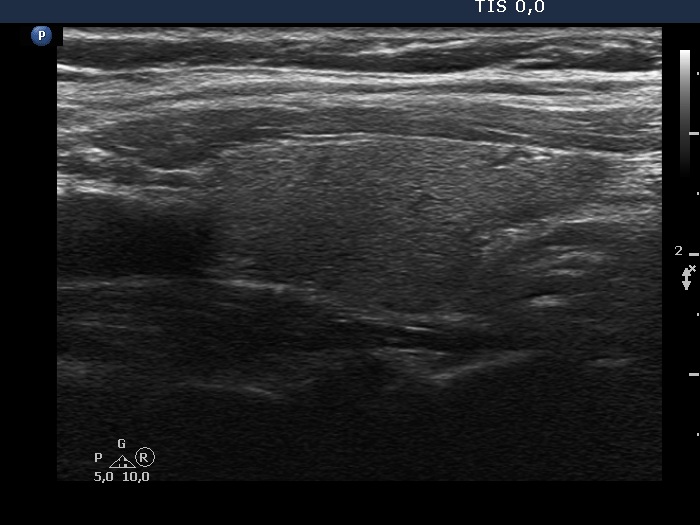

Intranodular hyperechogenic figures - case 2174 (ultrasonographic picture 5)

Left lobe, longitudinal view.